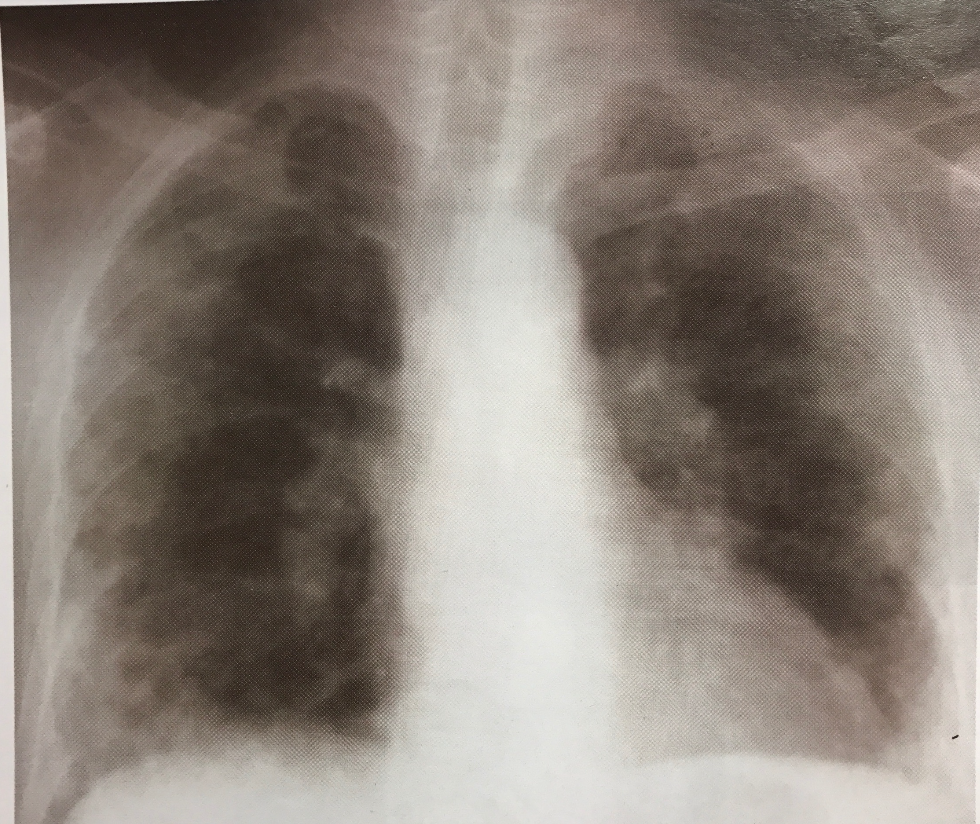

T de pulmón

Ao, cava, corazón, pericardio visceral, traquea, esof, vertebras

irresecable en Ca pulmón

T4 salvo limitada a:

N3 - SIEMPRE

M1 salvo 1 met en cerebro, pulmon o Suprarrenal y primario resecable

µcítico salvo I